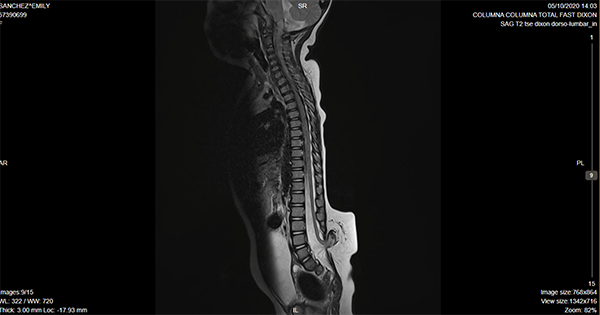

Caso ilustrativo n°3: Houkin tipo 3(Figura 3)

Paciente de 21 meses de vida, con diagnóstico de lipomielomeningocele lumbosacro, pie equinovaro bilateral. Urodinamia alterada con globo vesical asociado a pérdida de orina, cateterismo intermitente 3 veces/día. Potenciales evocados de miembros inferiores con alteración de la vía somestésica. Se realizó cirugía de desanclaje medular. Paciente permaneció en decúbito ventral 12 días con peso en herida. Posteriormente presentó colección de LCR en colgajo a los 7 días. La cual no fistulizó ni requirió punciones. Se manejó con tratamiento conservador y evolucionó favorablemente. Alta a los 14 días de la cirugía.

Se consideró Houkin tipo 3 por ser esperable, ya que la colección de LCR en este tipo de cirugías es muy frecuente, más allá del cierre hermético de la duramadre.

Figura 3:

Imagen por Resonancia Magnética de columna lumbosacra donde se evidencia disrafismo lumbar, compatible con lipomielomeningocele.